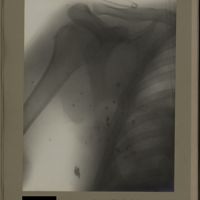

0122 - Page 10 - [Radiographie de l'épaule et du thorax]0122 - Page 10 - [Radiographie de l'épaule et du thorax]

0123 - Page 11 - [Radiographies de l'épaule]0123 - Page 11 - [Radiographies de l'épaule]